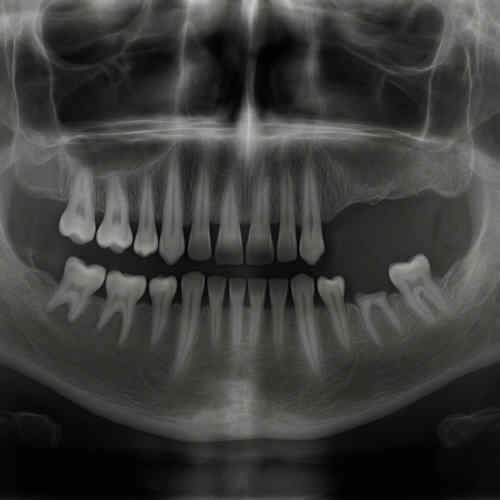

Kieferatrophie entwickelt sich schleichend. Erste Anzeichen sind Veränderungen des Zahnhalteapparats, instabiler Zahnersatz oder sichtbare Einsenkungen der Kieferlinie. Bei fortgeschrittener Atrophie treten funktionelle Einschränkungen wie Kauprobleme und Sprachveränderungen auf. Die Diagnostik erfolgt in der Regel durch bildgebende Verfahren wie Röntgenaufnahmen oder 3D-Scans, die das Ausmaß des Knochenabbaus sichtbar machen.